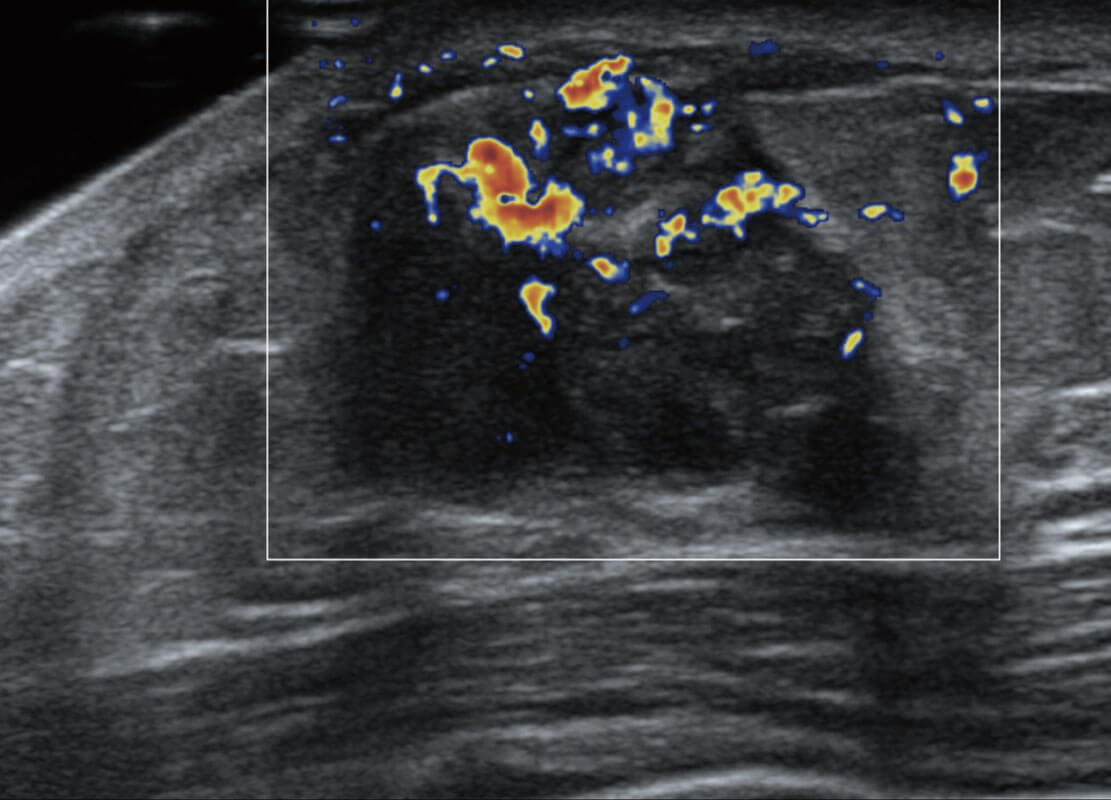

P60搭載寬頻帶線(xiàn)陣探頭、寬景成像、彈性成像技術(shù),為您提供乳腺應(yīng)用方案。P60支持高頻相控陣探頭、線(xiàn)陣探頭、腹部高頻探頭、腹部微凸探頭等,豐富的探頭群搭載敏感的彩色血流成像,適用于新生兒多種臟器檢測(cè)要求,滿(mǎn)足新生兒篩查需求。

乳腺導(dǎo)管癌

乳腺癌顯微血流